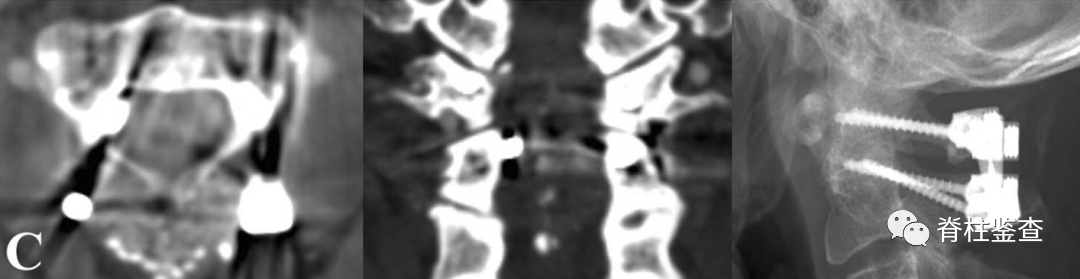

C:使用C2内侧开窗技术置入螺钉

D:尽管螺钉进入椎管,但未导致神经功能损伤案例二女性,29岁

C:通过C2内侧开窗技术技术进行C1-C2融合;术后神经功能完好,JOA评分17分